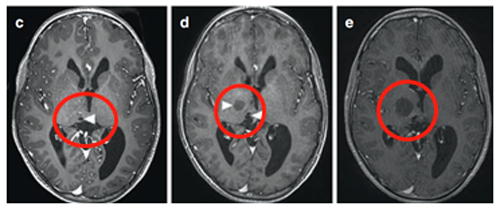

患儿在13岁时进行了神经导航和超声引导下的活检,证实为脑瘤为WHO I级,毛细胞星形细胞瘤。肿瘤囊肿持续扩大(图3),患儿发展为急性偏瘫。

(图3)

示同侧内囊(负责人体肢体运动)前外侧移位(箭头)(图4)。超声引导下将Ommaya导管和储层插入肿瘤囊性部分。

(图4)

术后MRI显示囊性占位接触,脑室慢慢恢复正常。(图5j)四个月后,由于患儿的偏瘫没有改善,Rutka教授为其行经胼胝体半球间入路及肿瘤次全切除术。

术后影像(图5),术后患儿偏瘫改善,患儿生长和智力发育正常,近期随访显示脑瘤未复发。免疫组化检测RAFV600E突变免疫无阳性,H3K27M阴性。

(图5)